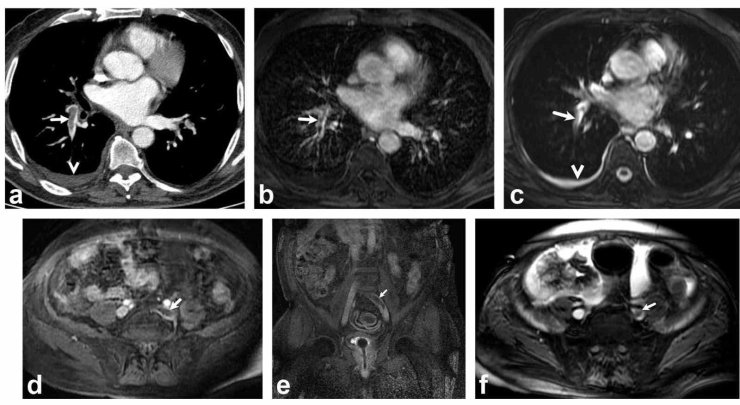

Bir dönem Denizli Tekden Hastanesinde de çalışan ve çalışmalarına ABD'de devam Dr. Nevzat Karabulut ve ekibinin yaptığı, British Journal of Radiology dergisinde yayımlanan "Diagnostic performance of contrast-enhanced and unenhanced combined pulmonary artery MRI and magnetic resonance venography techniques in the diagnosis of venous thromboembolism" başlıklı araştırmada manyetik rezonans (MR) yöntemi kullanılarak hem akciğer damarlarının hem de pıhtının kaynağı olan bacak toplardamarlarının aynı anda, tek bir incelemede değerlendirilebileceği gösterildi. Toplam 44 hastanın incelendiği çalışmada elde edilen sonuçlar oldukça dikkat çekti.

Kontrastlı MR yöntemi, hastaların tamamında akciğer embolisini doğru şekilde tespit ederken; kontrastsız MR yöntemi de yüksek doğruluk oranına ulaştı ve önemli ölçüde güvenilir sonuçlar verdi. Bu bulgular, radyasyon içermeyen MR yönteminin pıhtı hastalığını saptamada güçlü bir alternatif olduğunu ortaya koydu. Özellikle Radyasyon riskinin daha önemli olduğugenç hastalarda ve gebelerde MR'ın güvenli ve etkili bir seçenek olabileceği vurgulandı.